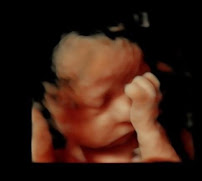

Baby Bump Imaging

Baby Bump Imaging is a Photography located in Baby Bump Imaging, 612 SW 3rd St Suite D, Lee's Summit, MO 64063